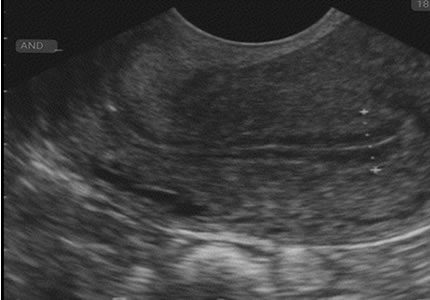

Comprehensive pelvic ultrasound evaluations for a wide range of non-pregnancy female health concerns, symptoms, or referrals.

Routine & Diagnostic Gynaecological Scans